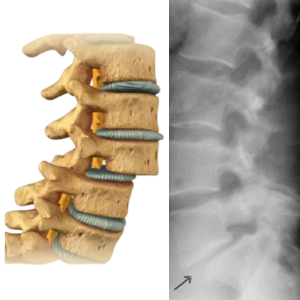

শিশু অর্থোপেডিকস